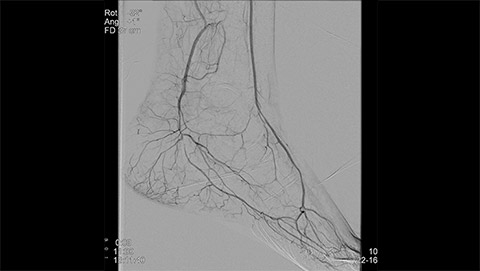

Whether treating critical limb ischemia, embolizing an uterine fibroid, or performing a biopsy or Endovascular Aneurysm Repair (EVAR) procedure, speed, clarity, and efficient dose management are key. Our multimodality Live Image Guidance solutions deliver critical information to optimize real-time guidance through complex vasculature and visualize tissue perfusion to identify treatment end-point in peripheral vascular interventions. At the same time, our AlluraClarity family with ClarityIQ technology enables physicians to deliver fast, effective, and simplified procedures with an efficient clinical workflow. All while delivering equivalent image quality at a fraction of the dose Sign up to receive exclusive updates on Live Image Guidance.

Dynamic 3D Roadmap provides a sustainable 3D roadmap to support interventional procedures. Dynamic 3D Roadmap matches the real-time 2D fluoroscopy images with the 3D-RA reconstruction of the vessel tree. It provides a 3D real-time insight of the advancement of the guide wire, catheter and coils through complex vessel structures. The Unsubtracted 3D Roadmap option reduces subtraction artifacts caused by patient breathing and movements, providing a clear roadmap during abdominal and thoracic interventions.

Live 3D Roadmap allows you to follow the advancement of guidewires, catheters and coils in real-time. It automatically adapts in real-time to changes in C-arm angulation and rotation, table movement, field of view and source-image distance.